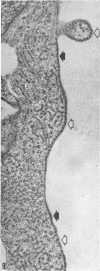

The ultrastructure of CV-1 cells infected with subacute sclerosing panencephalitis (SSPE) viruses was compared with that of CV-1 cells infected with the wild or Edmonston strain of measles virus. Both SSPE viruses and the measles viruses produced two types of nucleocapsid structures: smooth filaments, 15 to 17 nm in diameter, and granular filaments, 22 to 25 nm. The smooth and granular filaments produced by SSPE and measles virus did not differ in appearance. In CV-1 cells infected with SSPE viruses, smooth filaments formed large intranuclear inclusions and granular filaments occupied a large area of the cytoplasm, but always spared the area under the cell membrane. Particles budding from the surface of these cells contained no nucleocapsids. In CV-1 cells infected with measles virus, only small aggregates of smooth filaments were seen in the nuclei. Granular filaments in the cytoplasm predominantly occupied the area under the cell membrane, and were aligned beneath the cell membrane in a parallel fashion and assembled into budding particles. These differences between SSPE and measles virus may be regarded as quantitative, but they do distinguish SSPE viruses from measles virus. Moreover, the formation of large nuclear inclusions filled with smooth filaments appears to be a characteristic process of SSPE, but not of measles, since this type of inclusion is invariably seen in SSPE brain tissues, brain cultures derived from them, and CV-1 cells infected with SSPE viruses.